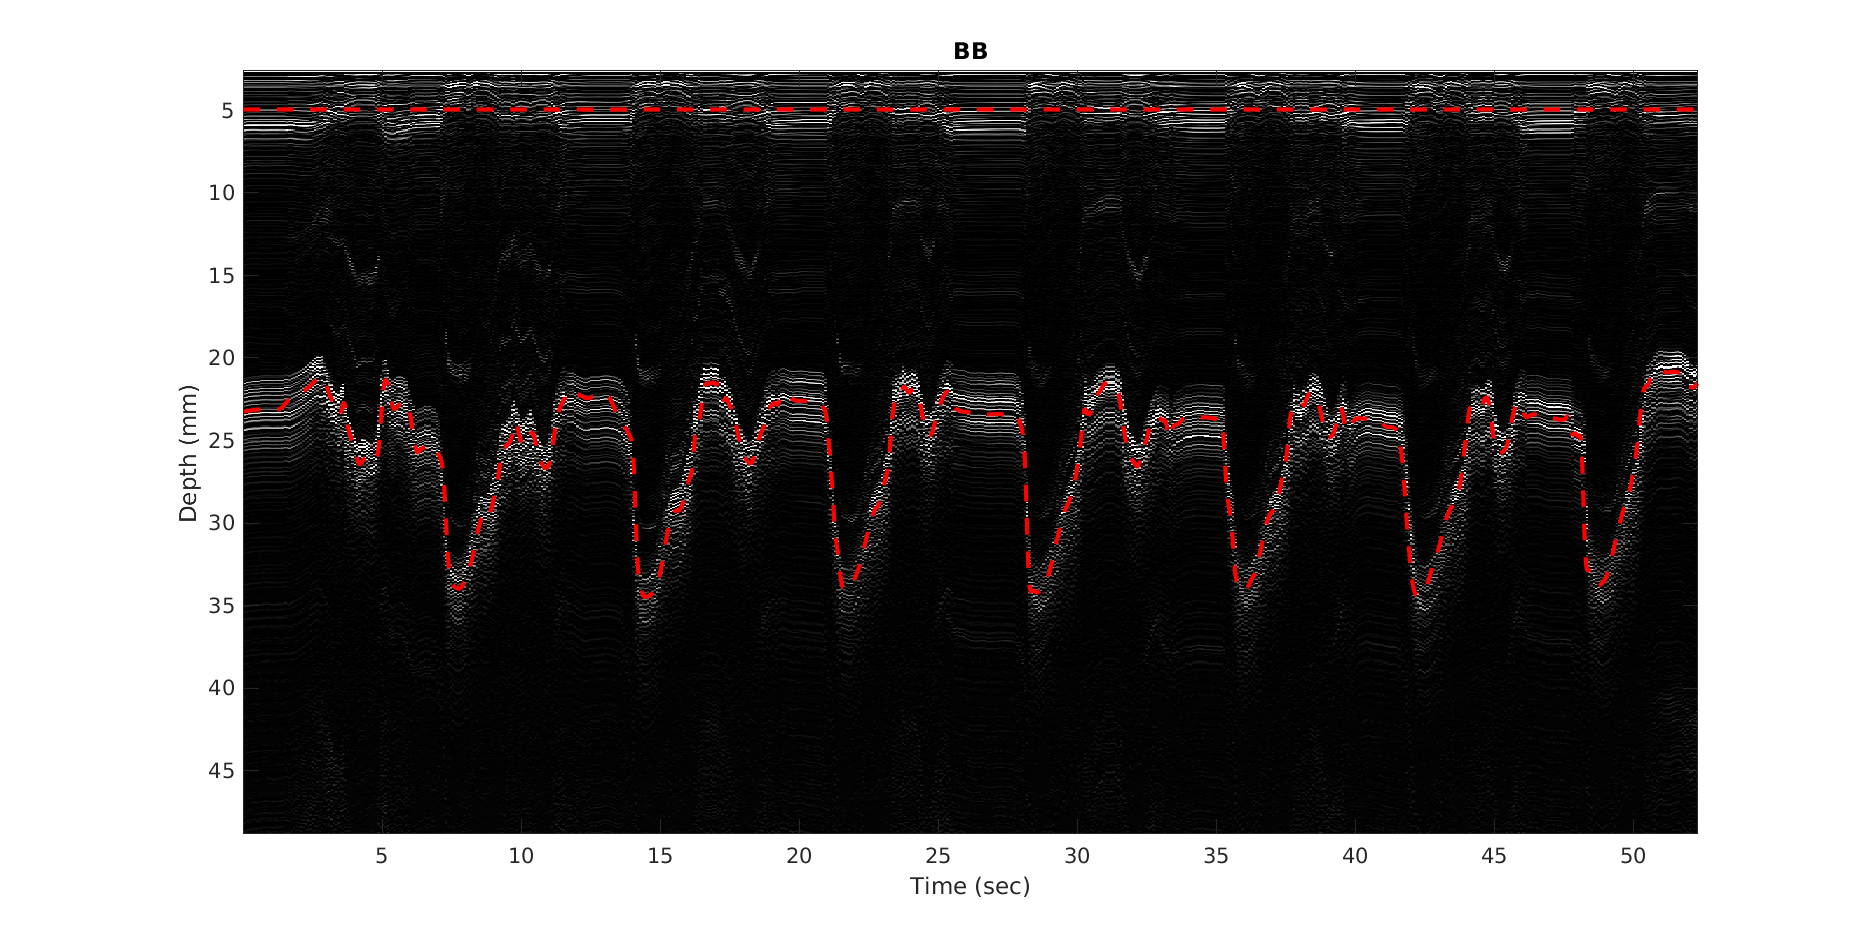

1. A模式超声技术

A模式超声技术是一种通过测量超声波在组织中传播的速度和时间来评估组织特性的方法。在本研究中,我们采用单元件超声换能器,通过连续发送超声波并接收反射信号,实时跟踪肌肉厚度的变化。

为了验证模型的准确性,我们首先进行了受控等速收缩实验。通过等速测力计控制关节的运动速度和力量,同时记录肌肉厚度变化和关节扭矩,用于模型的训练和验证。

1. 受控等速收缩实验结果

在受控等速收缩实验中,我们发现肌肉厚度变化与关节扭矩之间具有良好的相关性。通过建立的数学模型,我们在肘部和膝盖的扭矩估计中实现了小于7.6%的误差,决定系数(R²)大于0.92。